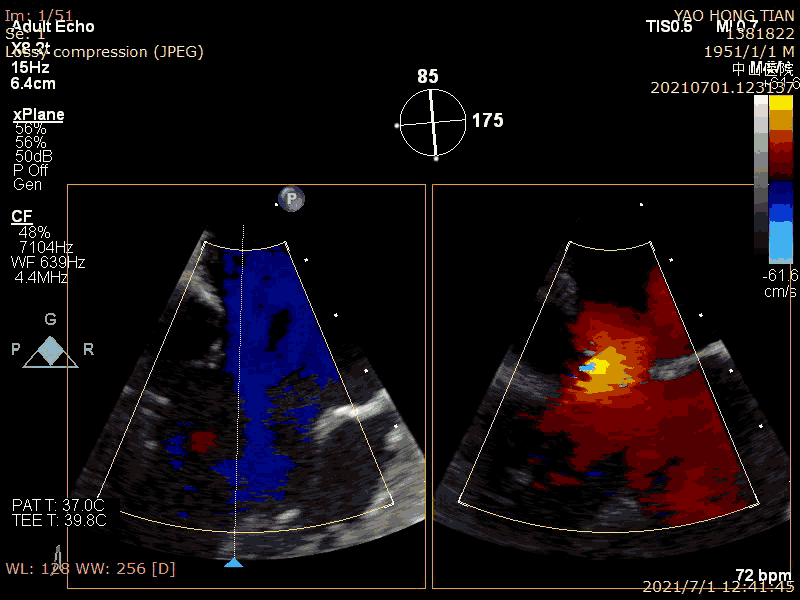

患者,男,70岁。术前超声诊断:左心室射血分数 LVEF 58%,左心室舒张末内径LVDD 52mm,左心房内径LAD 57mm,PASP 63mmHg,二尖瓣瓣尖错位导致重度二尖瓣反流,VC 6*13mm,反流面积19.8cm²(图1-2)。

术前大量反流(VC 6*13mm)

瓣尖错位导致A2P2大量反流